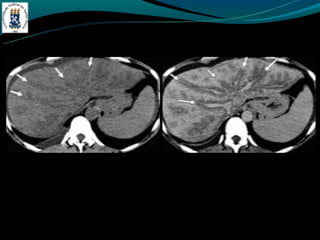

DOENÇA DO FÍGADOGORDUROSO -E uma resposta uma lesão e a toxina -Acúmulo de colesterol e triglicerídios -Alcoolismo, obesidade, desnutrição, hiperalimentação, costicóide, DM, pancreatite … -Exames de imagem é o melhor método -Avaliação: - TC: densidade menor do que do baço - RM: identificar esteatose focal -Esteatose focal - Distribuição segmentar, sub capsular, VB, lig falciforme - Margem nítida e em linha reta - Não desloca vasos

• 16.

• 17.